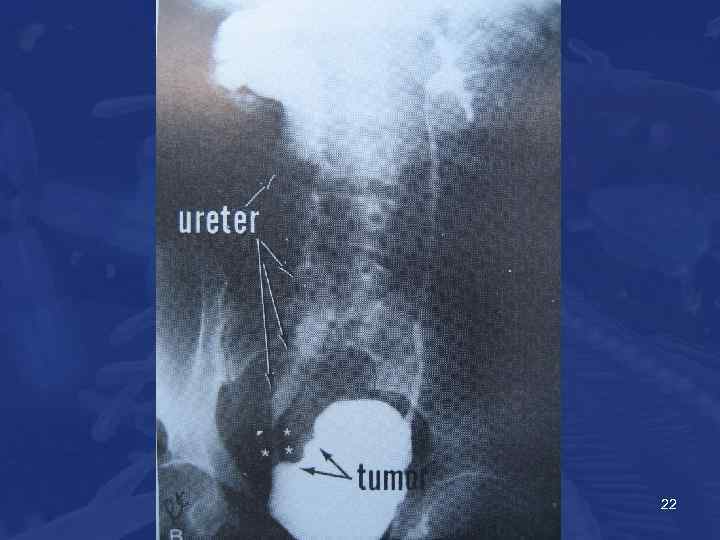

• • Опухоль м/п Диагностика Гематурия Учащенное мочеиспускание Осмотр пациента Дополнительные методы: ВВУ УЗИ СT Сканирование костей • Цитология мочи • Цистоскоция и ТУР 20

Опухоль м/п Recomendations • Physical examination (including digital rectal and pelvic examination) • Renal and bladder ultrasonography and/or IVP • Cystoscopy with description of the tumour: size, site, appearance (a diagram of the bladder should be included) • Urinalysis • Urinary cytology • TUR with: • biopsy of the underlying tissue • random biopsies in the presence of positive cytology, large or non-papillary tumour • biopsy of the prostatic urethra in cases of Tis or suspicion of it 24